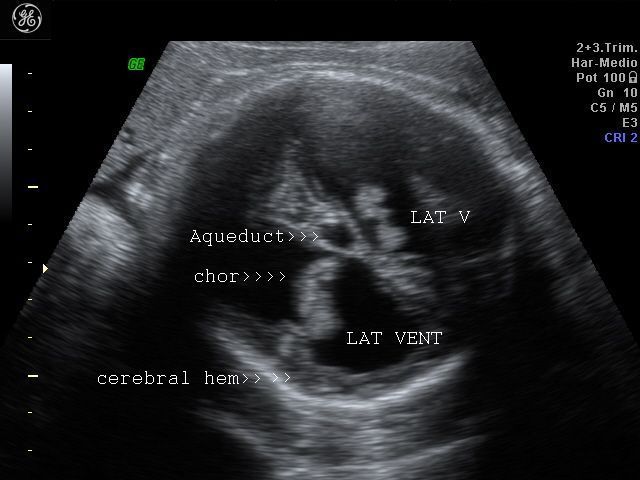

Aqueductal stenosis causing obstructive hydrocephalus

Sonography of the fetal brain done on this 3rd trimester fetus shows marked dilatation of the lateral ventricles bilaterally. The 3rd ventricle and upper part of the cerebral aqueduct or aqueduct of Sylvius are also dilated. The choroid plexus on both sides (within the lateral ventricles) appear to "dangle" or droop to the dependent part of the brain. The lateral ventricles measure more than 30 mm.     (3 cms.) on both sides at the level of the atria. The cerebral hemispheres show marked thinning of the cerebral tissue (both cortex and white matter), but are visualized as thin tissue along the cranial vault. Current literature holds that any fetal lateral ventricular measurement of more than 10 mm. (at the atria) is pathological. These ultrasound images suggest a diagnosis of aqueductal stenosis with intraventricular obstructive hydrocephalus. (Ultrasound images taken with GE Voluson machine are courtesy of  Dr. Martin Horenstein, MD, Argentina).

The main criteria used to diagnose hydrocephalus/ ventriculomegaly are: 1) atrial size (greater than 10 mm.) 2) Ventricle to cerebral hemisphere ratio ( normal ranging from 74 % at 16 weeks to 35 % by 25 weeks). 3) The combined anterior horn width (normal = less than 20 mm.)